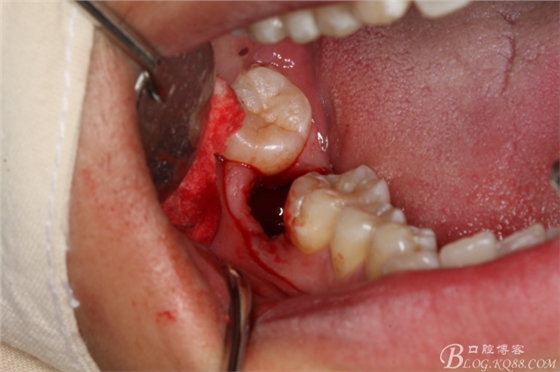

圖7.不切開、不翻瓣、利用有限空間直接高速牙鉆分牙

圖8.先橫斷47牙冠,盡量從牙頸部橫斷

圖9.潛掘法橫斷牙冠